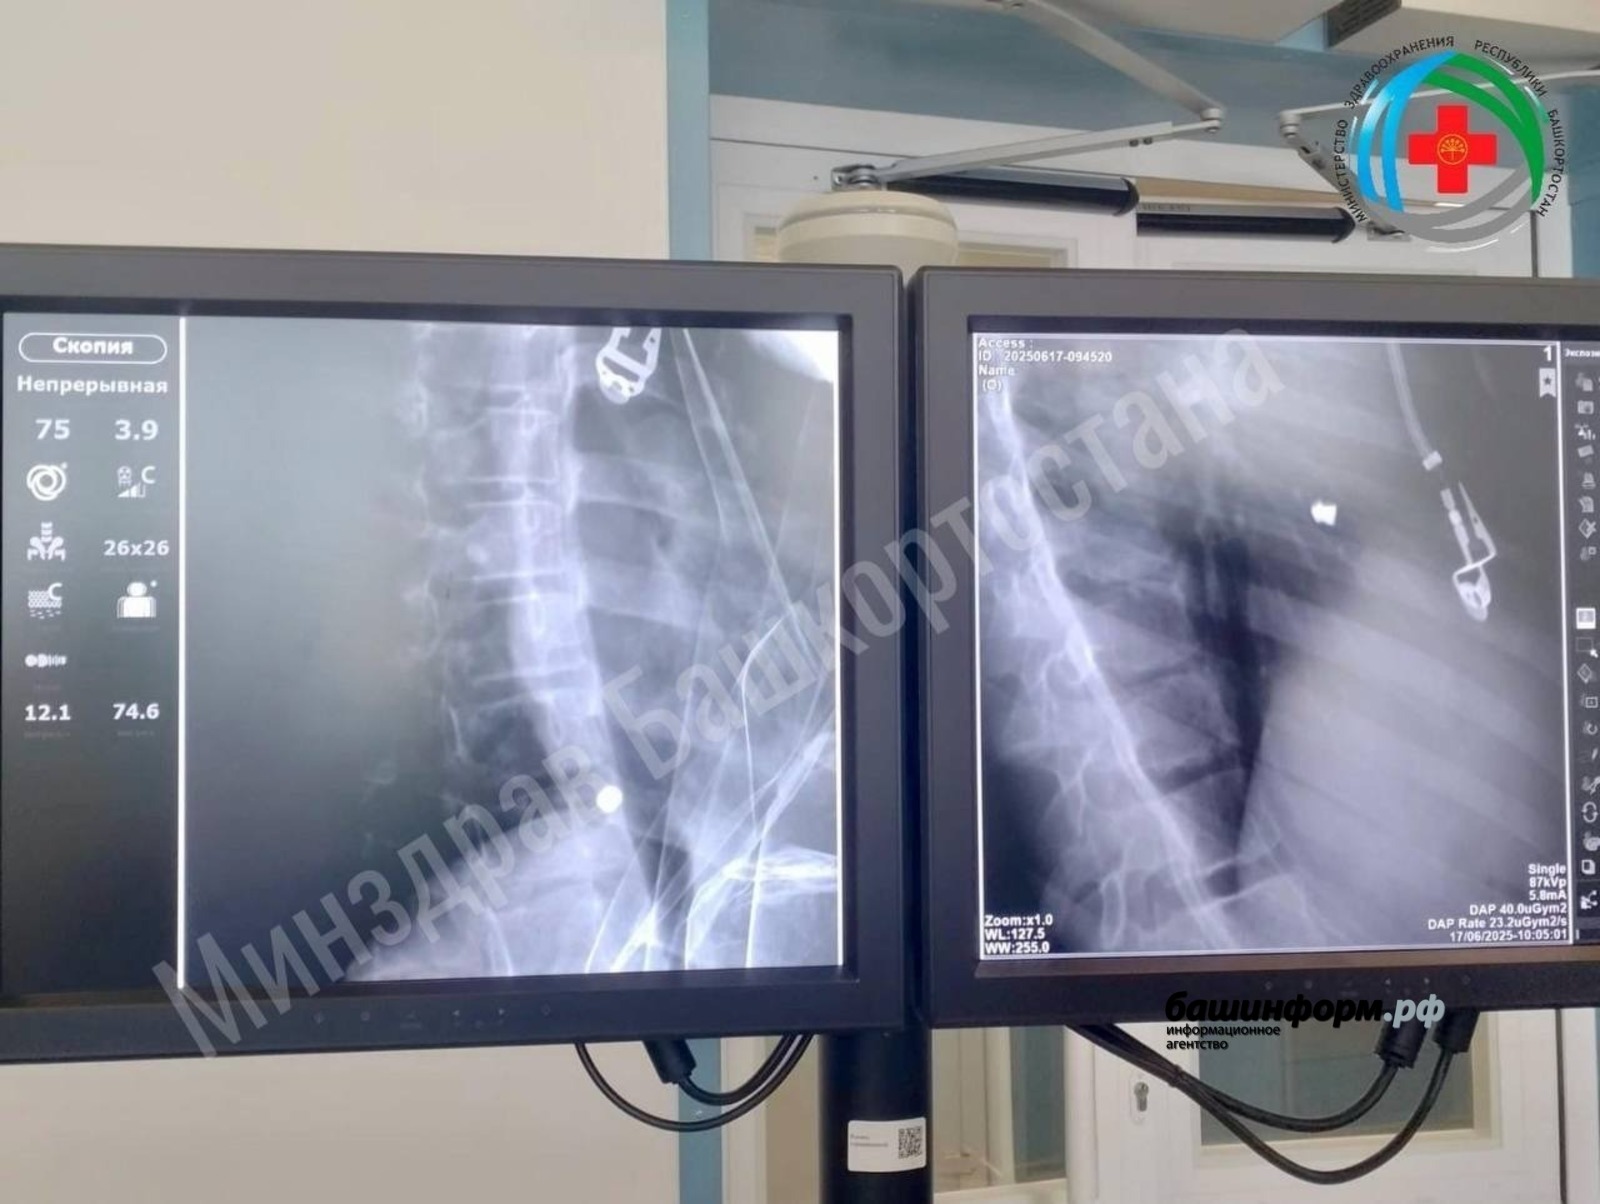

Ранее «Башинформ» информировал о том, что девочка получила ранение по неосторожности. Инцидент произошел в Иглинском районе в результате несчастного случая с пневматическим оружием. Скорая помощь доставила ребенка в РДКБ в тяжелом состоянии с проникающим ранением сердца и травмой легкого. Пациентка чувствовала сильную слабость, боли при глотании и дыхании. Медики экстренно провели торакотомию — операцию по вскрытию грудной клетки и успешно извлекли пулю. После операции девочку перевели в кардиоцентр для дальнейшего наблюдения и лечения.